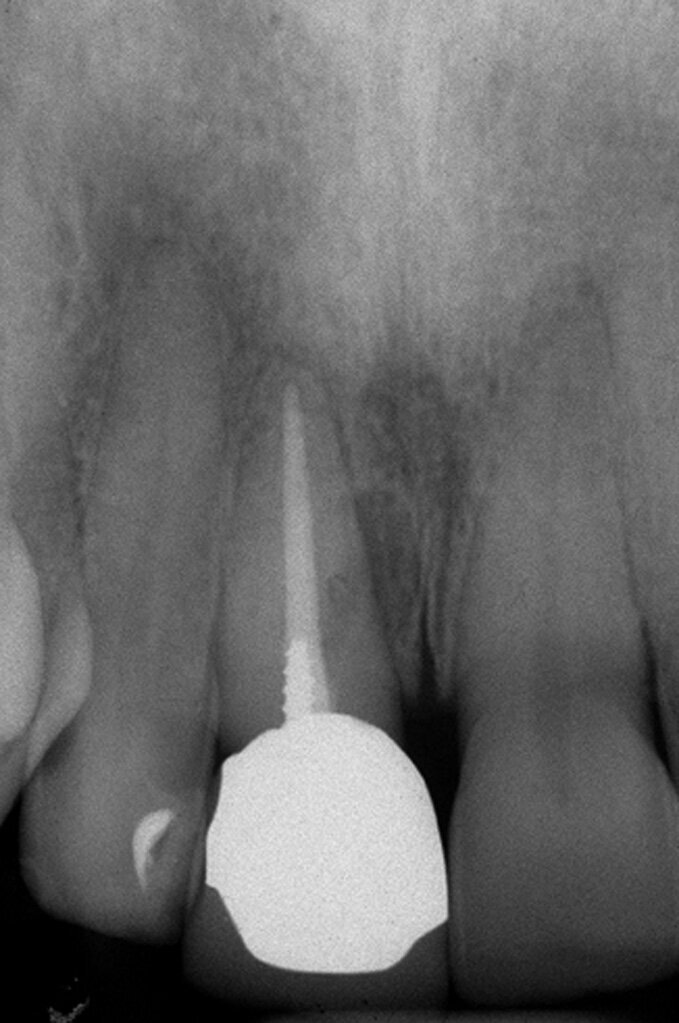

Le perforazioni del terzo medio avvengono nella maggior parte dei casi durante la preparazione della cavità d’accesso o, più spesso, durante le fasi di detersione e sagomatura o infine durante la preparazione dello spazio per un perno con l’utilizzo di frese tipo Largo, Peeso, Gates Glidden o simili (Figg. 2a-2f).